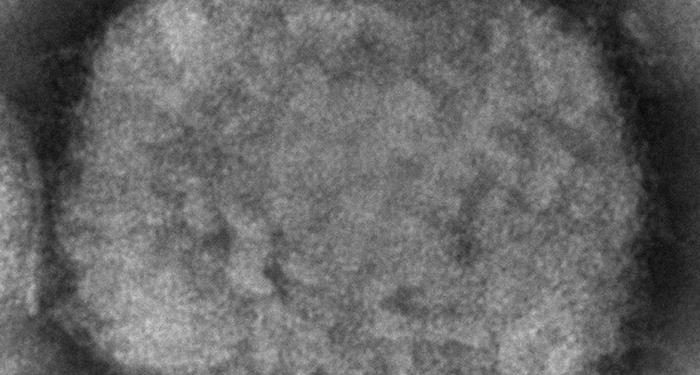

Monkeypox is from the same family as the now-eradicated smallpox virus and is endemic to nine African countries. The zoonotic virus primarily spreads through close contact with bodily fluids and usually requires prolonged contact to spread.